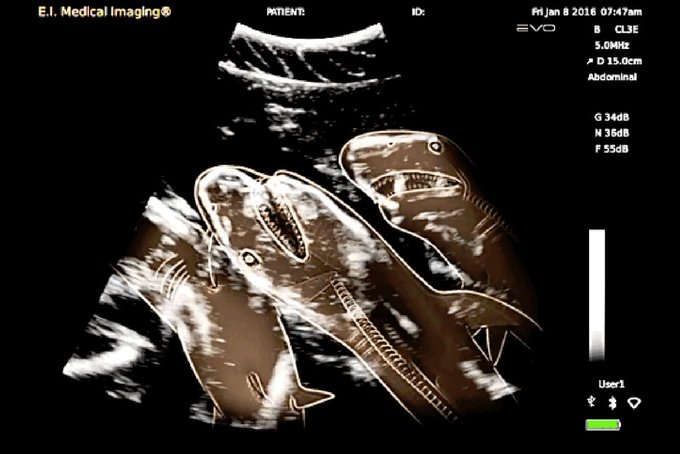

Беременная акула (снимок УЗИ).